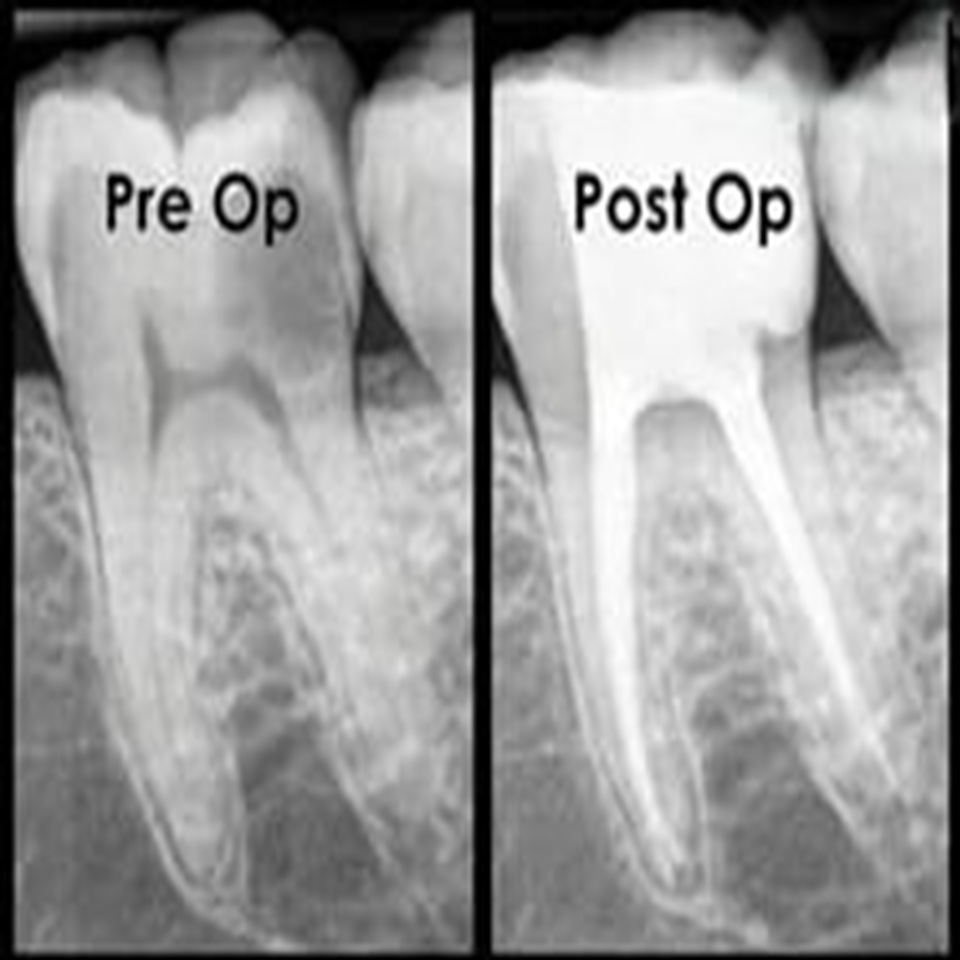

Endodontics is a specialized branch of dentistry focused on diagnosing and treating problems related to the tooth pulp and root canals. The most common procedure is root canal therapy, which removes infected or inflamed pulp to relieve pain, eliminate infection, and save the natural tooth. At our clinic, we use advanced and minimally invasive techniques to provide precise, comfortable, and effective treatments that protect your long-term oral health.

Endodontic care plays a vital role in saving teeth affected by deep decay, cracks, or injury. Using modern diagnostic tools, digital imaging, and magnification, we carefully clean and disinfect the canals, then seal them to prevent reinfection. These advanced methods ensure greater accuracy, less discomfort, and faster healing.